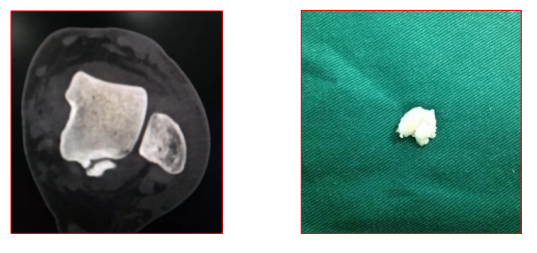

病例二、有症状距后三角骨

疼痛性距后三角骨。川汇区杨脑村人 男、25岁、散打运动员,比赛后疼痛一周,加重三天, 无法行走。

保守治疗:消炎、止痛类药物应用,休息,深部热疗 一周,症状消失。

踝关节后方撞击引起的疼痛性距后三角骨,也有学者 称其为:三角骨综合征。

治疗以保守治疗为主。包括制动休息,冷敷(即RICE 原则);予以非甾体抗炎药;限制足底弯曲;以及物 理治疗和特定运动康复。

对难治性患者,可采用手术治疗。包括切除骨赘及软组织清理等。可以选择开放性手术或关节镜手术,两者在手术结果 上没有差异。但关节镜下手术并发症少,能更快返回到日常活动中。